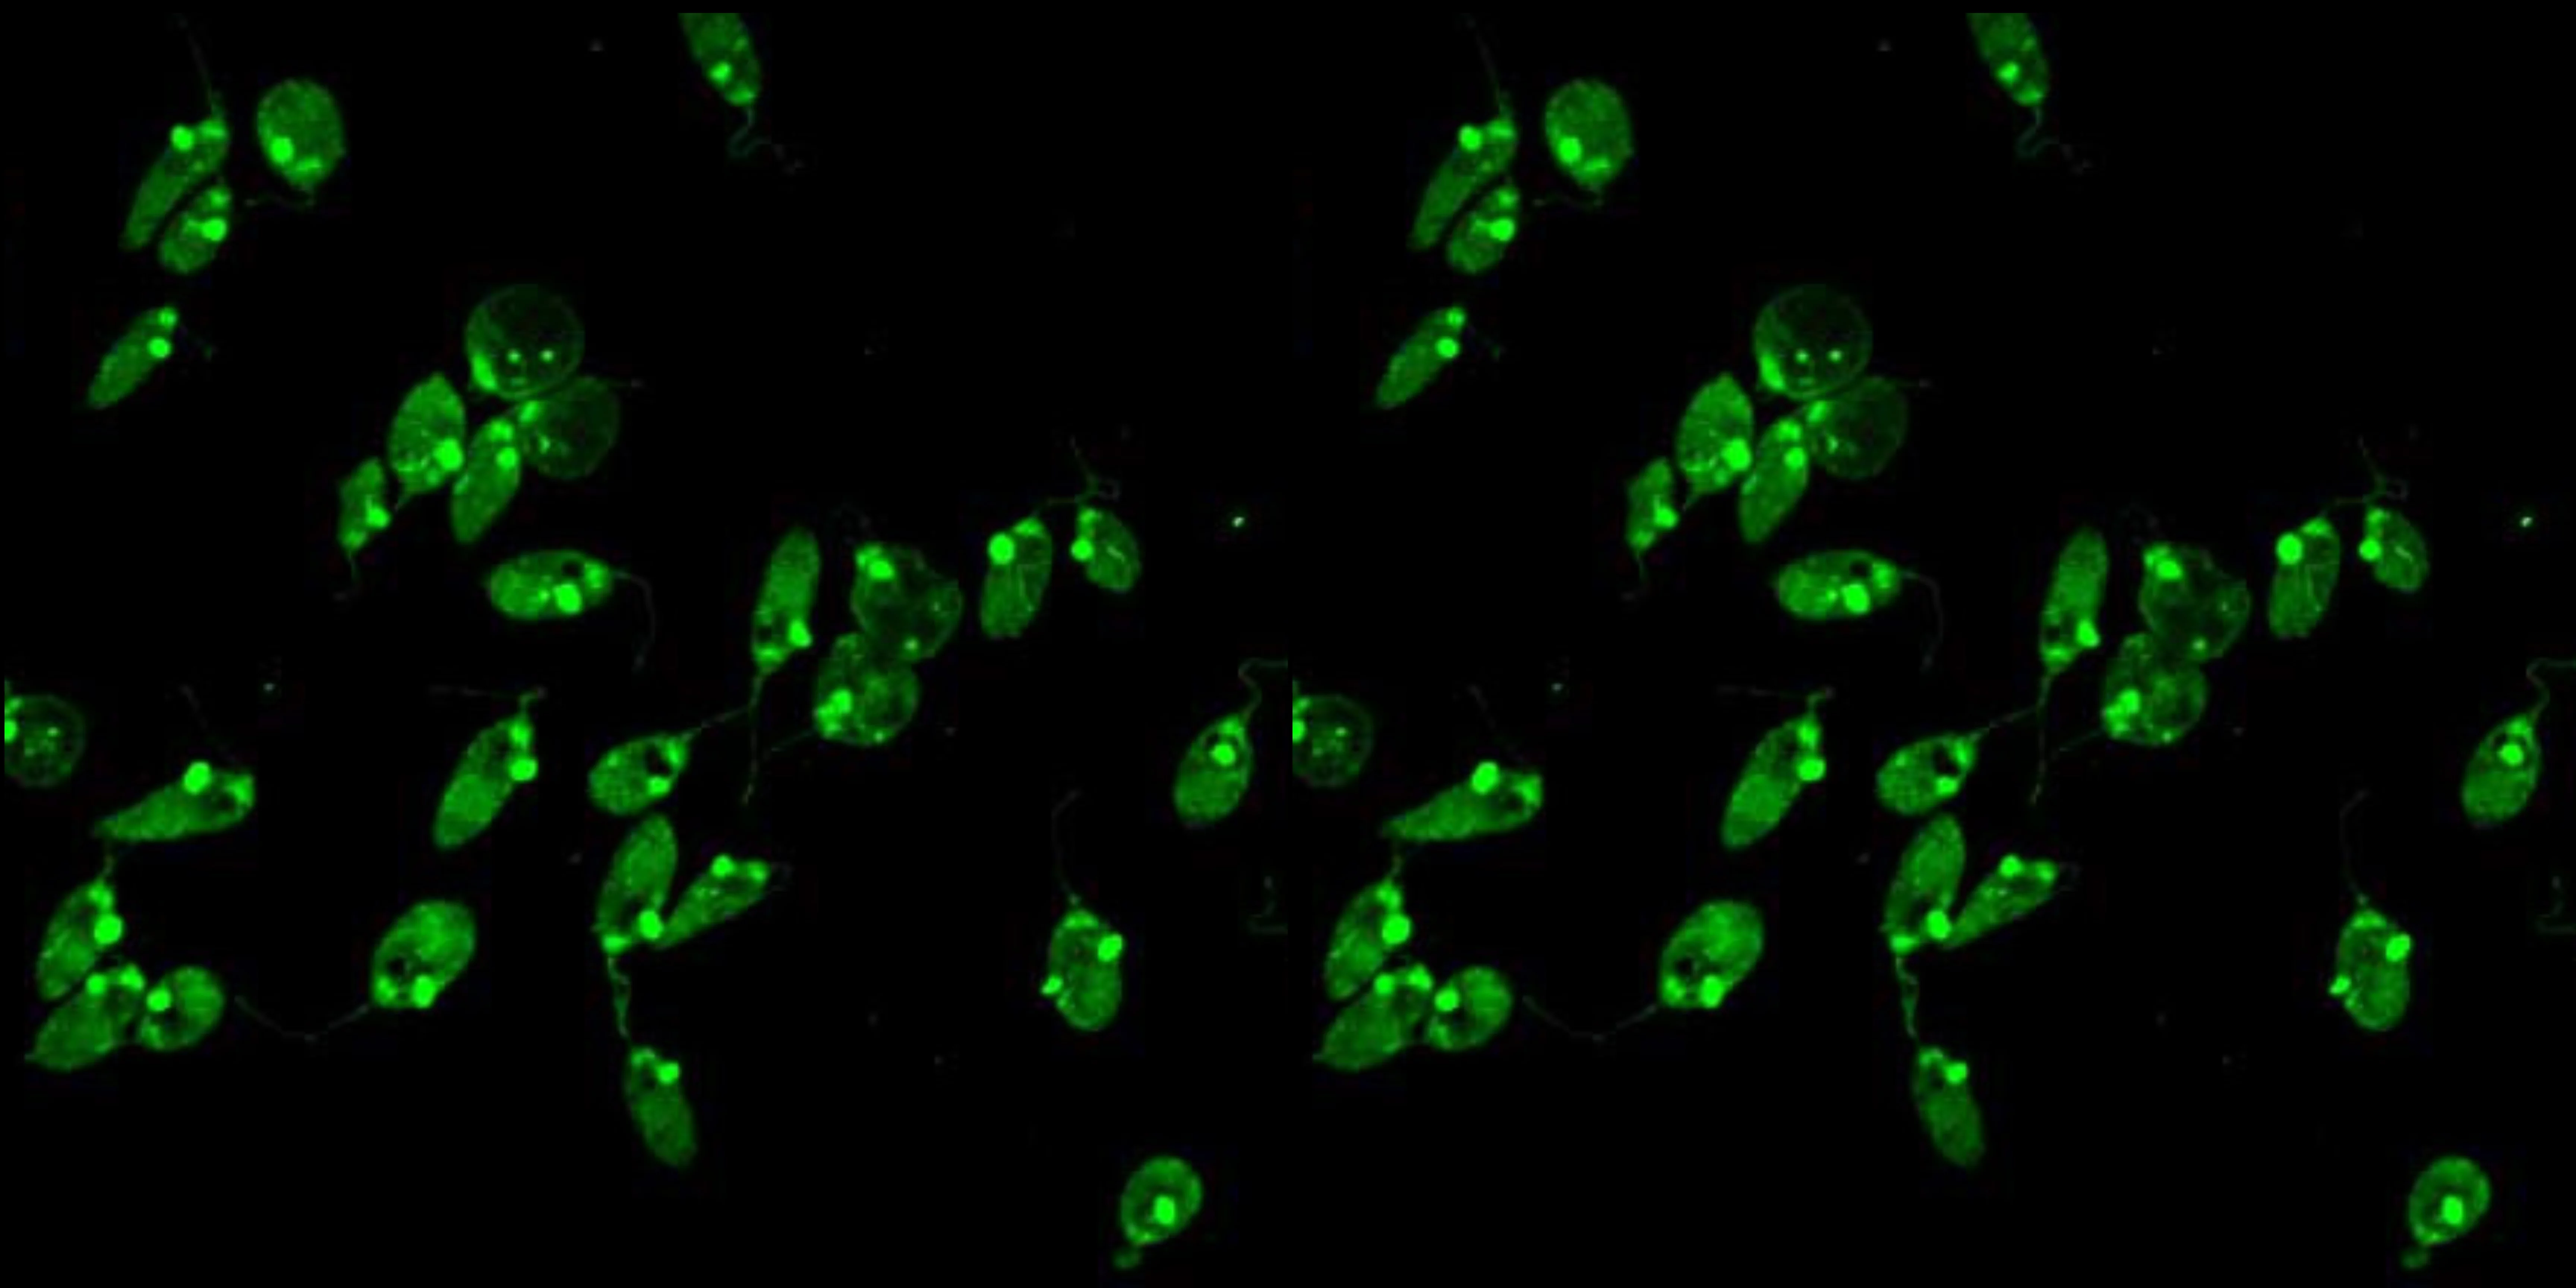

Injúria Renal Aguda (revisão Lancet 2025)

Injúria Renal Aguda (revisão Lancet 2025)